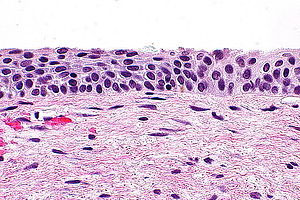

Atrophy

Altered squamous maturation 2/2 hormonal deficiency (menopause or prepuberty)

Micro: can produce several patterns:

Typical: thin epithelium c lack of maturation c uniform basal and parabasal cells and inc NC, dense chromatin, no / rare mits, little-mild pleomorphism

Atrophy with partial maturation: cytoplasmic glycogen and large evenly spaced nuclei and scattered mits

Pseudokoilocytosis (aka postmenopausal squamous atypia) hyperchromatic nuclei c even chromatin, binucleation, and cytoplasmic halos c more uniform size and shape than HPV

IHC: Ki67 <20% in basal 1/3, <5% in middle 1/3 and absent in superficial cells (vs in SIL)

- negative: p16 (vs SIL)

Cerix c atrophy